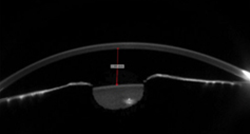

02안내렌즈삽입술 수술 전·후 검사

안내렌즈삽입술에는 각막의 전후면, 전방, 수정체 등 전안부에 대한 정확한 정보가 필요하며 수술 후에는 렌즈가 바른 위치에 고정되어 있는지 정기적으로 확인해야 합니다. Sirius는 렌즈가 삽입되는 전안부에 대한 정밀검사가 가능하므로 수술 전 부작용 예방 및 안전한 안내렌즈삽입술을 위한 필수 검사장비입니다.